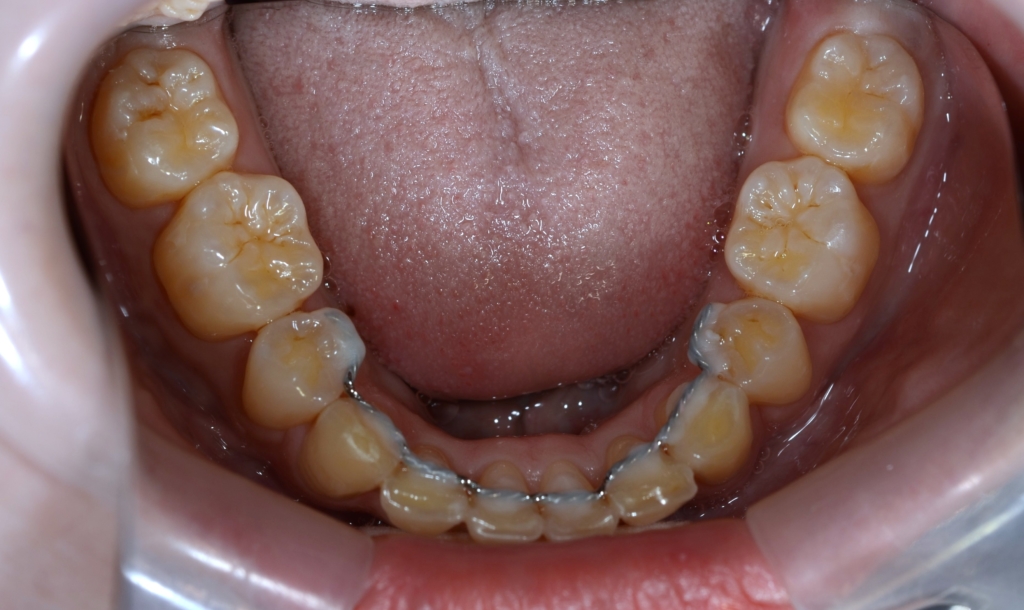

【保定】 上下ともフィックスタイプ&クリアリテーナー

【治療期間】 3年2カ月間

【治療費用】 87万6千円

【治療装置】 ハーフホワイトtypeのマルチブラケットシステム、

アンカースクリューを計4本

PLAS & パラタルバー